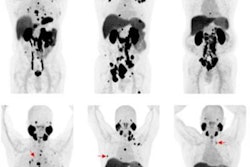

Functional imaging with PET/MRI is better than anatomic imaging alone for detecting prostate cancer in men who have a significantly higher chance of developing the disease, according to research published August 31 in Radiology.

Israeli researchers conducted a head-to-head comparison of sensitivity, specificity, and accuracy prior to biopsy between multiparametric MRI and PET/MRI with a radiotracer based on gallium-68 (Ga-68) prostate-specific membrane antigen (PSMA). They found the specificity of Ga-68 PSMA PET/MRI was higher for detecting cancer in men with elevated prostate-specific antigen (PSA) levels.

The researchers found that specificity was 76% for Ga-68 PSMA PET/MRI compared with 49% for multiparametric MRI for detecting clinically significant prostate cancer. Sensitivity was similar between the two approaches. For PI-RADS 3 lesions, specificity was also higher for Ga-68 PSMA PET/MRI than for multiparametric MRI at 86% versus 59%.